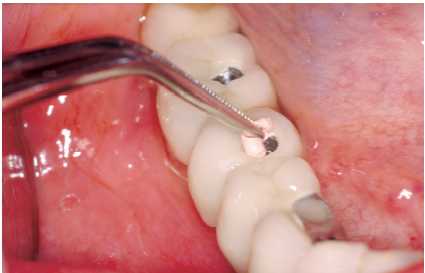

— Eliminación de placa bacteriana y/o cálculo

con curetas de plástico, oro, titanio o carbono composite

(Figura 3), puntas de ultrasonido de carbono composite (Figura

4). No se debe emplear ningún instrumento con punta

metálica, ya que se corre el riesgo de arañar

la superficie del implante y crear nichos en los que proliferen

las bacterias.

Figura 3. Limpieza de implante con cureta de carbono